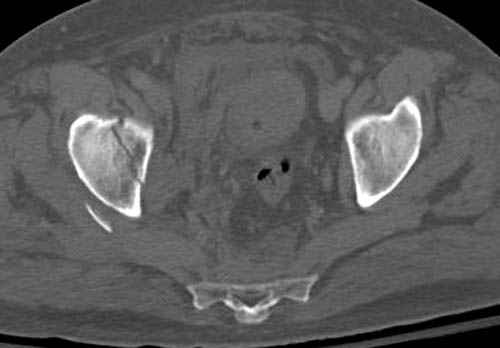

Дополнительно имеется перелом ацетабулума: задняя

колонна с полупоперечным переломом, и переломы костей лица.

На седьмой день зафиксирован перелом ацетабулума через задний доступ. Перед операцией для профилактики DVT, IVC фильтер, также получает Lovenox.

По снимку создается впечатление о высоком поперечном переломе, задней колонны, стенки; почему не пользовались *magic screw*?